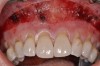

Various procedures to correct deficient gingival contours have been well documented in the dental literature.1,2 Increasing zones of attached gingiva using palatal donor tissue and the free gingival grafting procedure was introduced by Björn almost a half century ago.3 Using palatal donor tissue in the form of a free soft-tissue autograft for root-coverage procedures was reported by Miller.4 Additional procedures were reported using lateral5 or coronal repositioning6-8 of the adjacent attached gingiva via a pedicle flap or the coronal repositioning of previously grafted tissue.9,10 Miller also reported on gingival grafts placed over root surfaces to correct areas of deep-wide gingival recession.11 Further surgical advancements led to the use of subepithelial connective tissue from the palate to obtain root coverage.12-14 Figure 1 shows the pretreatment view of a mandibular central incisor, and Figure 2 depicts the post-treatment view of the site treated with a subepithelial connective tissue graft harvested from the patient’s palatal tissues.

Fig 2. Post-treatment clinical view after subepithelial connective tissue graft.

Figure 2